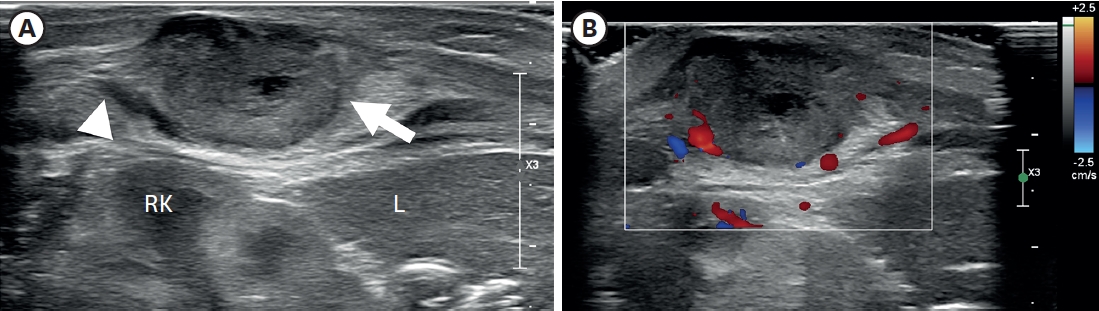

Fig. 2.Axial images of chest magnetic resonance imaging. (A) A lobulated soft tissue lesion (arrow) in the muscular layer of the body wall, just outside the right kidney and liver, with the internal cystic or necrotic portion on the T2-weighted image. The solid portion of the lesion shows (A) slightly high signal intensity compared with muscle on the T2-weighted image and (B) iso signal intensity on the T1-weighted image. T1-weighted axial images with fat suppression before (C) and after (D) contrast enhancement show only the lesion’s peripheral wall enhancement without filling the contrast material.

Fig. 1) showed a lobulated soft tissue lesion in the muscular layer, with an internal necrotic hypoechoic portion. Magnetic resonance imaging (MRI,

Fig. 2) also showed a lobulated mass with central necrosis, a well-defined margin, and peripheral rim enhancement in the muscular layer. The patient underwent surgical excision on the 20th day of birth for accurate diagnosis and treatment. In the operative findings, the mass was located in the latissimus dorsi muscle and butted to the right 12th rib, but dissection was performed without difficulties or injury to adjacent structures.

The radiologic findings of PM are also not specific [

11]. In this case, the preoperative US showed internal hypoechoic lesions, and the MRI also showed an internal hyperintense portion on the T2-weighted image, which suggested internal necrosis. These lesions were proven to be central degeneration without hemorrhage or necrosis. These findings have not been reported previously, and they could be one of the possible radiologic findings of PM.